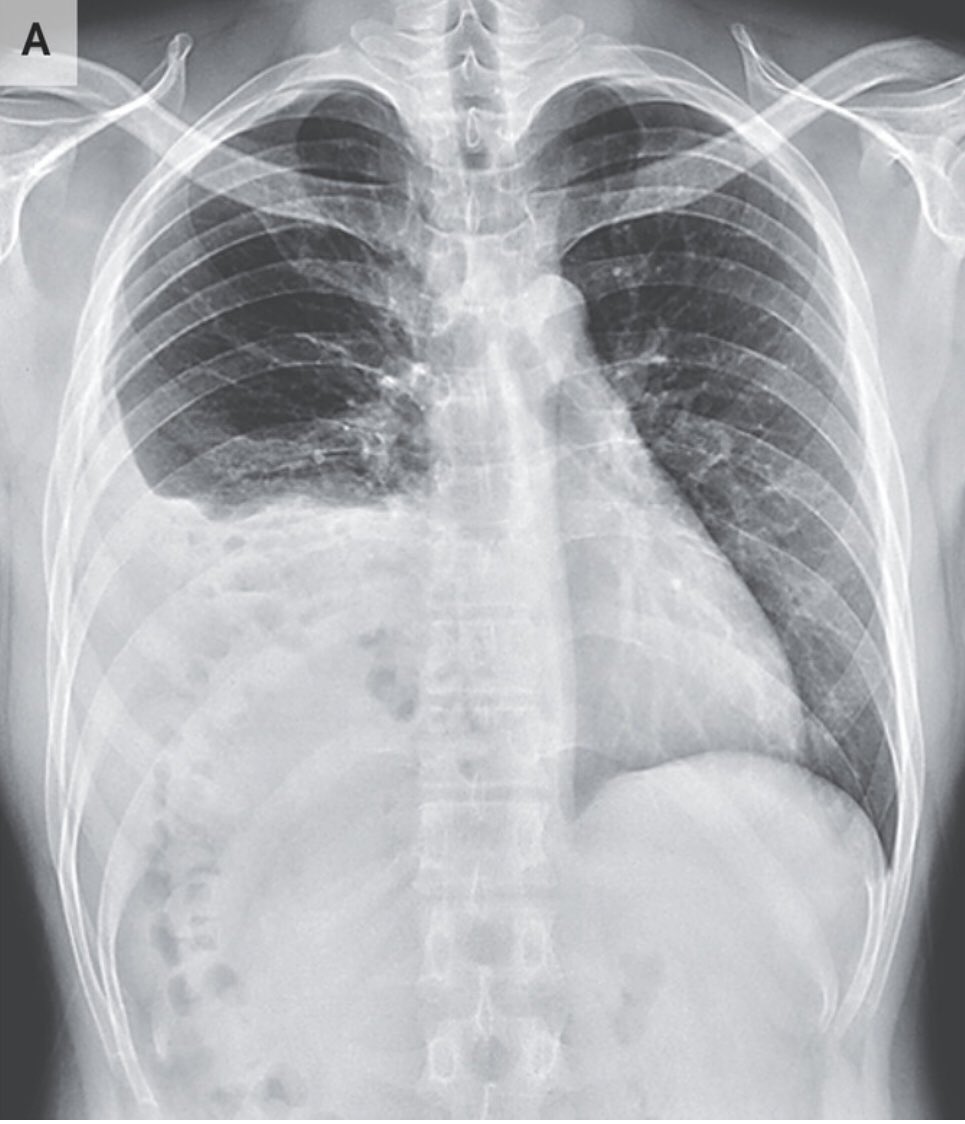

و النص اليمين من الحجاب الحاجز طالع لفوق شوية جهة الصدر (elevated right hemidiaphragm)

القولون كان قاعد في فوق في محل ما محلو (translocation of the colon into the right upper quadrant of the abdomen)

و السبب هو عيب خُلقي في الحجاب الحاجز

التشخيص الإتعمل للشاب دا هو انو عندو فتق بوكدالك، او فتق حجابي خلقي

congenital diaphragmatic hernia due to a posterolateral diaphragmatic defect-Bochdalek hernia

في العادة العيانيين بيتعرفو و بيتشخصو صغار عشان الاعراض البيعملها الفتاق

في حالات نادرة ممكن تكون من غير اعراض و المريض يكبر بيها و عندها العرض الممكن يجي بيه العيان هو انسداد معوي